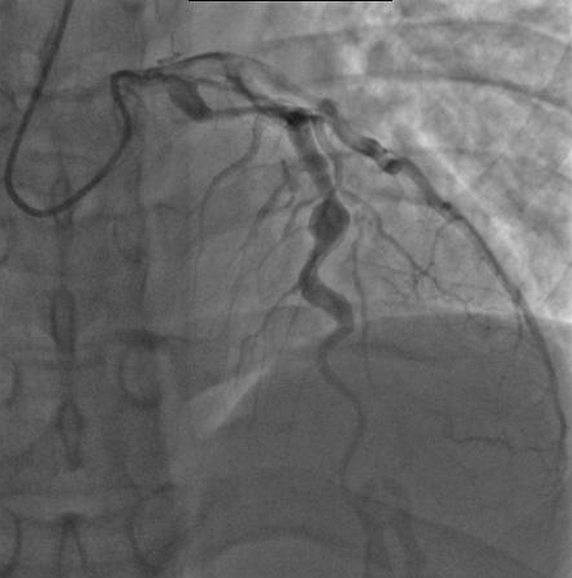

인체 내에서 중간 정도 크기의 동맥에 염증이 발생할 수 있으며, 그 중 심장근육에 혈액을 공급하는 관상동맥에 영향을 끼칠 수 있으므로 관상동맥의 확장이 있는지 심장초음파를 통해 확인한다.

초기에는 급성 열성 질환(급성기)으로 전신의 혈관 벽에 염증이 발생하며, 대부분 1~2주 내에 증상이 완화되지만 1개월 정도로 길어지는 경우도 있다. 염증이 심할 때는 겨드랑이나 사타구니의 혈관에 동맥류가 생기는 경우도 있다. 심장 혈관의 염증으로 인해 관상동맥의 시작 부분 근처와 좌관상동맥의 좌전하행지 및 좌회선지의 분기 부근에 동맥류가 생기기 쉽다.

- 혈관 조영술: 과거 관상 동맥 동맥류 진단에 사용되었으나, 현재는 심장 초음파 검사로 대체되는 추세이다.

심장 합병증은 가와사키병의 가장 중요한 문제이며, 미국과 일본에서 소아기에 발생하는 심장 질환의 주요 원인이다.[135] 선진국에서는 급성 류마티스열을 대체하여 소아에서 발생하는 후천성 심장 질환의 가장 흔한 원인이 된 것으로 보인다.[13] 치료받지 않은 어린이의 20~25%에서 관상동맥류가 혈관염의 후유증으로 발생한다.[47] 이는 질병 발생 평균 10일째에 처음 감지되며 관상동맥 확장 또는 동맥류의 최대 발생 빈도는 발병 후 4주 이내에 발생한다.[43] 동맥류는 소형(혈관벽의 내경 <5 mm), 중형(직경 5–8 mm), 거대형(직경 > 8 mm)으로 분류된다.[135] 낭상 및 방추형 동맥류는 일반적으로 질병 발병 후 18~25일 사이에 발생한다.[13]

가와사키병으로 인한 관상동맥 병변은 시간이 지남에 따라 역동적으로 변화한다.[7] 관상동맥류가 있는 혈관의 절반에서 질병 발병 후 1~2년 이내에 회복이 관찰되었다.[54][55] 혈관벽의 치유 과정의 결과로 발생하는 관상동맥의 협착은 종종 혈관의 심각한 폐쇄와 심장이 충분한 혈액과 산소를 공급받지 못하게 한다.[54] 이는 결국 심근 조직의 사망, 즉 심근 경색(MI)으로 이어질 수 있다.[54]

동맥류, 협착 또는 동맥류와 협착이 모두 있는 관상동맥 내 혈전성 폐쇄로 인한 MI는 가와사키병으로 인한 주요 사망 원인이다.[56] MI의 가장 높은 위험은 질병 발병 후 첫 해에 발생한다.[56] 소아의 MI는 성인의 증상과 다른 증상을 보인다. 주요 증상은 쇼크, 불안, 구토, 복통이었으며, 흉통은 나이가 많은 어린이에게서 가장 흔하게 나타났다.[56] 이러한 어린이의 대부분은 수면 중 또는 휴식 중에 발작이 발생했으며, 발작의 약 3분의 1은 무증상이었다.[13]

관상 동맥 손상(협착)으로 인해 혈행이 충분히 확보되지 않는 경우 (심근 허혈)는 외과 수술로 치료를 한다. 구체적으로는 카테터를 이용한 경피적 관상 동맥 성형술(PTCA)과 관상 동맥 우회술(CABG)이 있으며, 발병 후 2년 이내에 시행하면 치료 효과가 높다. 한편, 발병 후 10여 년이 지나 혈관벽이 두꺼워지고 혈관 내부에 석회화가 진행된 경우에는 로터블레이터로 내벽을 깎아낸다. 그러나 카테터나 로터블레이터로 치료하면 다시 협착이 진행될 수 있다. 근본적인 치료는 관상 동맥 우회 수술이며, 심장으로의 혈행이 회복되면 운동 제한은 없어진다.